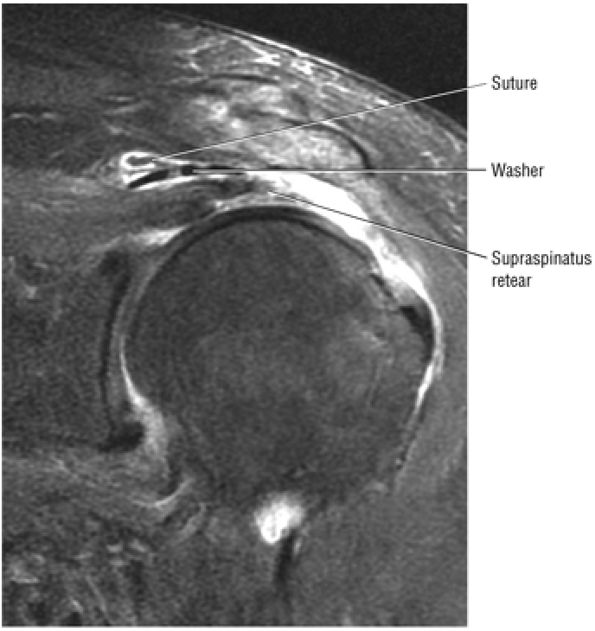

FIGURE 8.102 ● (A) The anterior undersurface of the acromion and the coracoacromial ligament form the coracoacromial arch. The subacromial subdeltoid bursa facilitates the passage of the rotator cuff and proximal humerus under the coracoacromial arch. (B) A superior axial image shows the anterior-to-posterior extent of the coracoacromial (CA) ligament perpendicular to the supraspinatus tendon. The fluid in the subacromial-subdeltoid bursa represents fluid between two serosal surfaces in contact with each other. One serosal surface is contributed by the undersurface of the coracoacromial arch and deltoid, and the other serosal surface is on the bursal side of the cuff.

|

![]() |